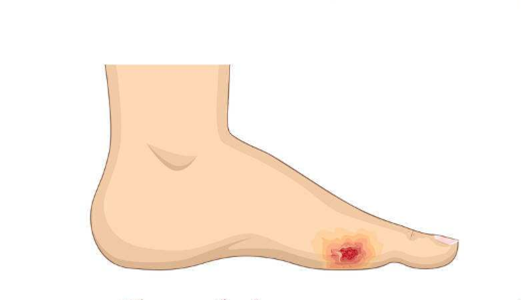

脈管炎

脈管炎症狀、原因、治療與預防保健 · 脈管炎完整疾病指南 · 脈管炎專業就醫指南

常見症狀:

患肢蒼白、發紺、疼痛

發病部位:

下肢

脈管炎圖片

脈管炎腳趾頭爛怎麼辦